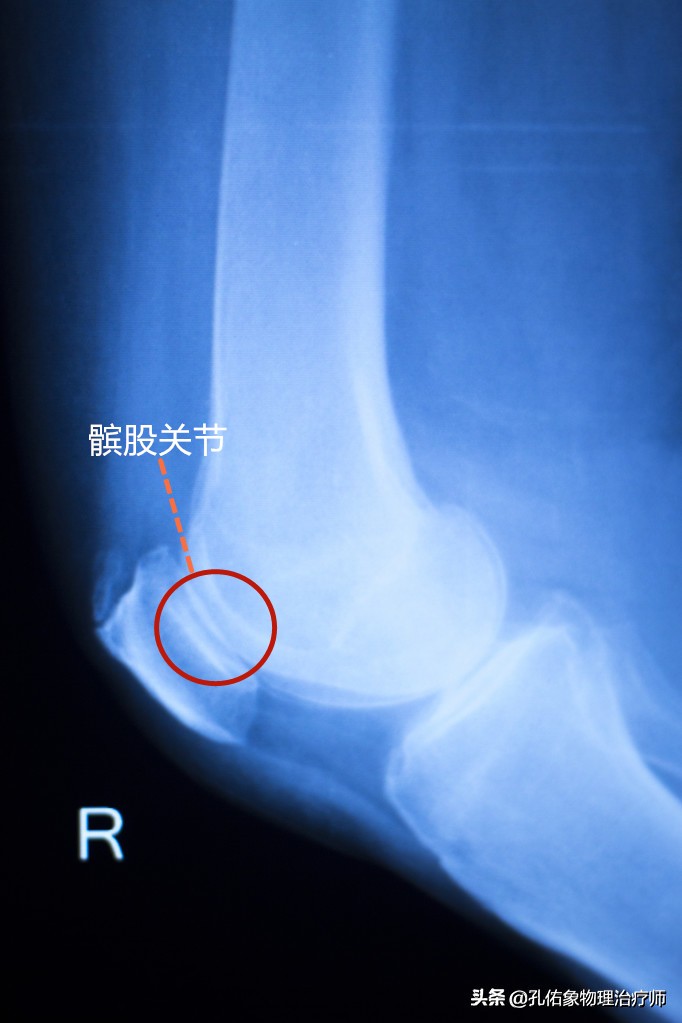

髌股关节

另一个构成人体膝关节复合体之一的关节,就是上图所示的大腿骨与膝盖骨连接的髌股关节,若是拍片后,它是长这样的,看下图:

X片髌股关节